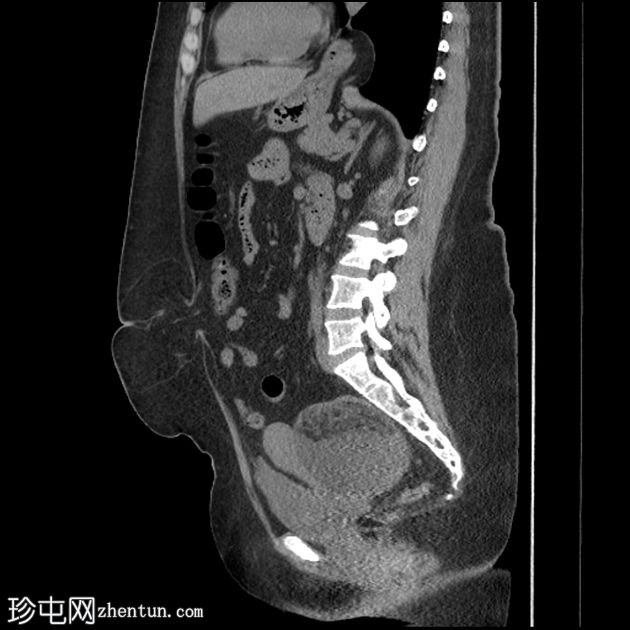

MRI

矢状位

T1加权像

盆腔可见部分囊性肿块,内含脂肪球。